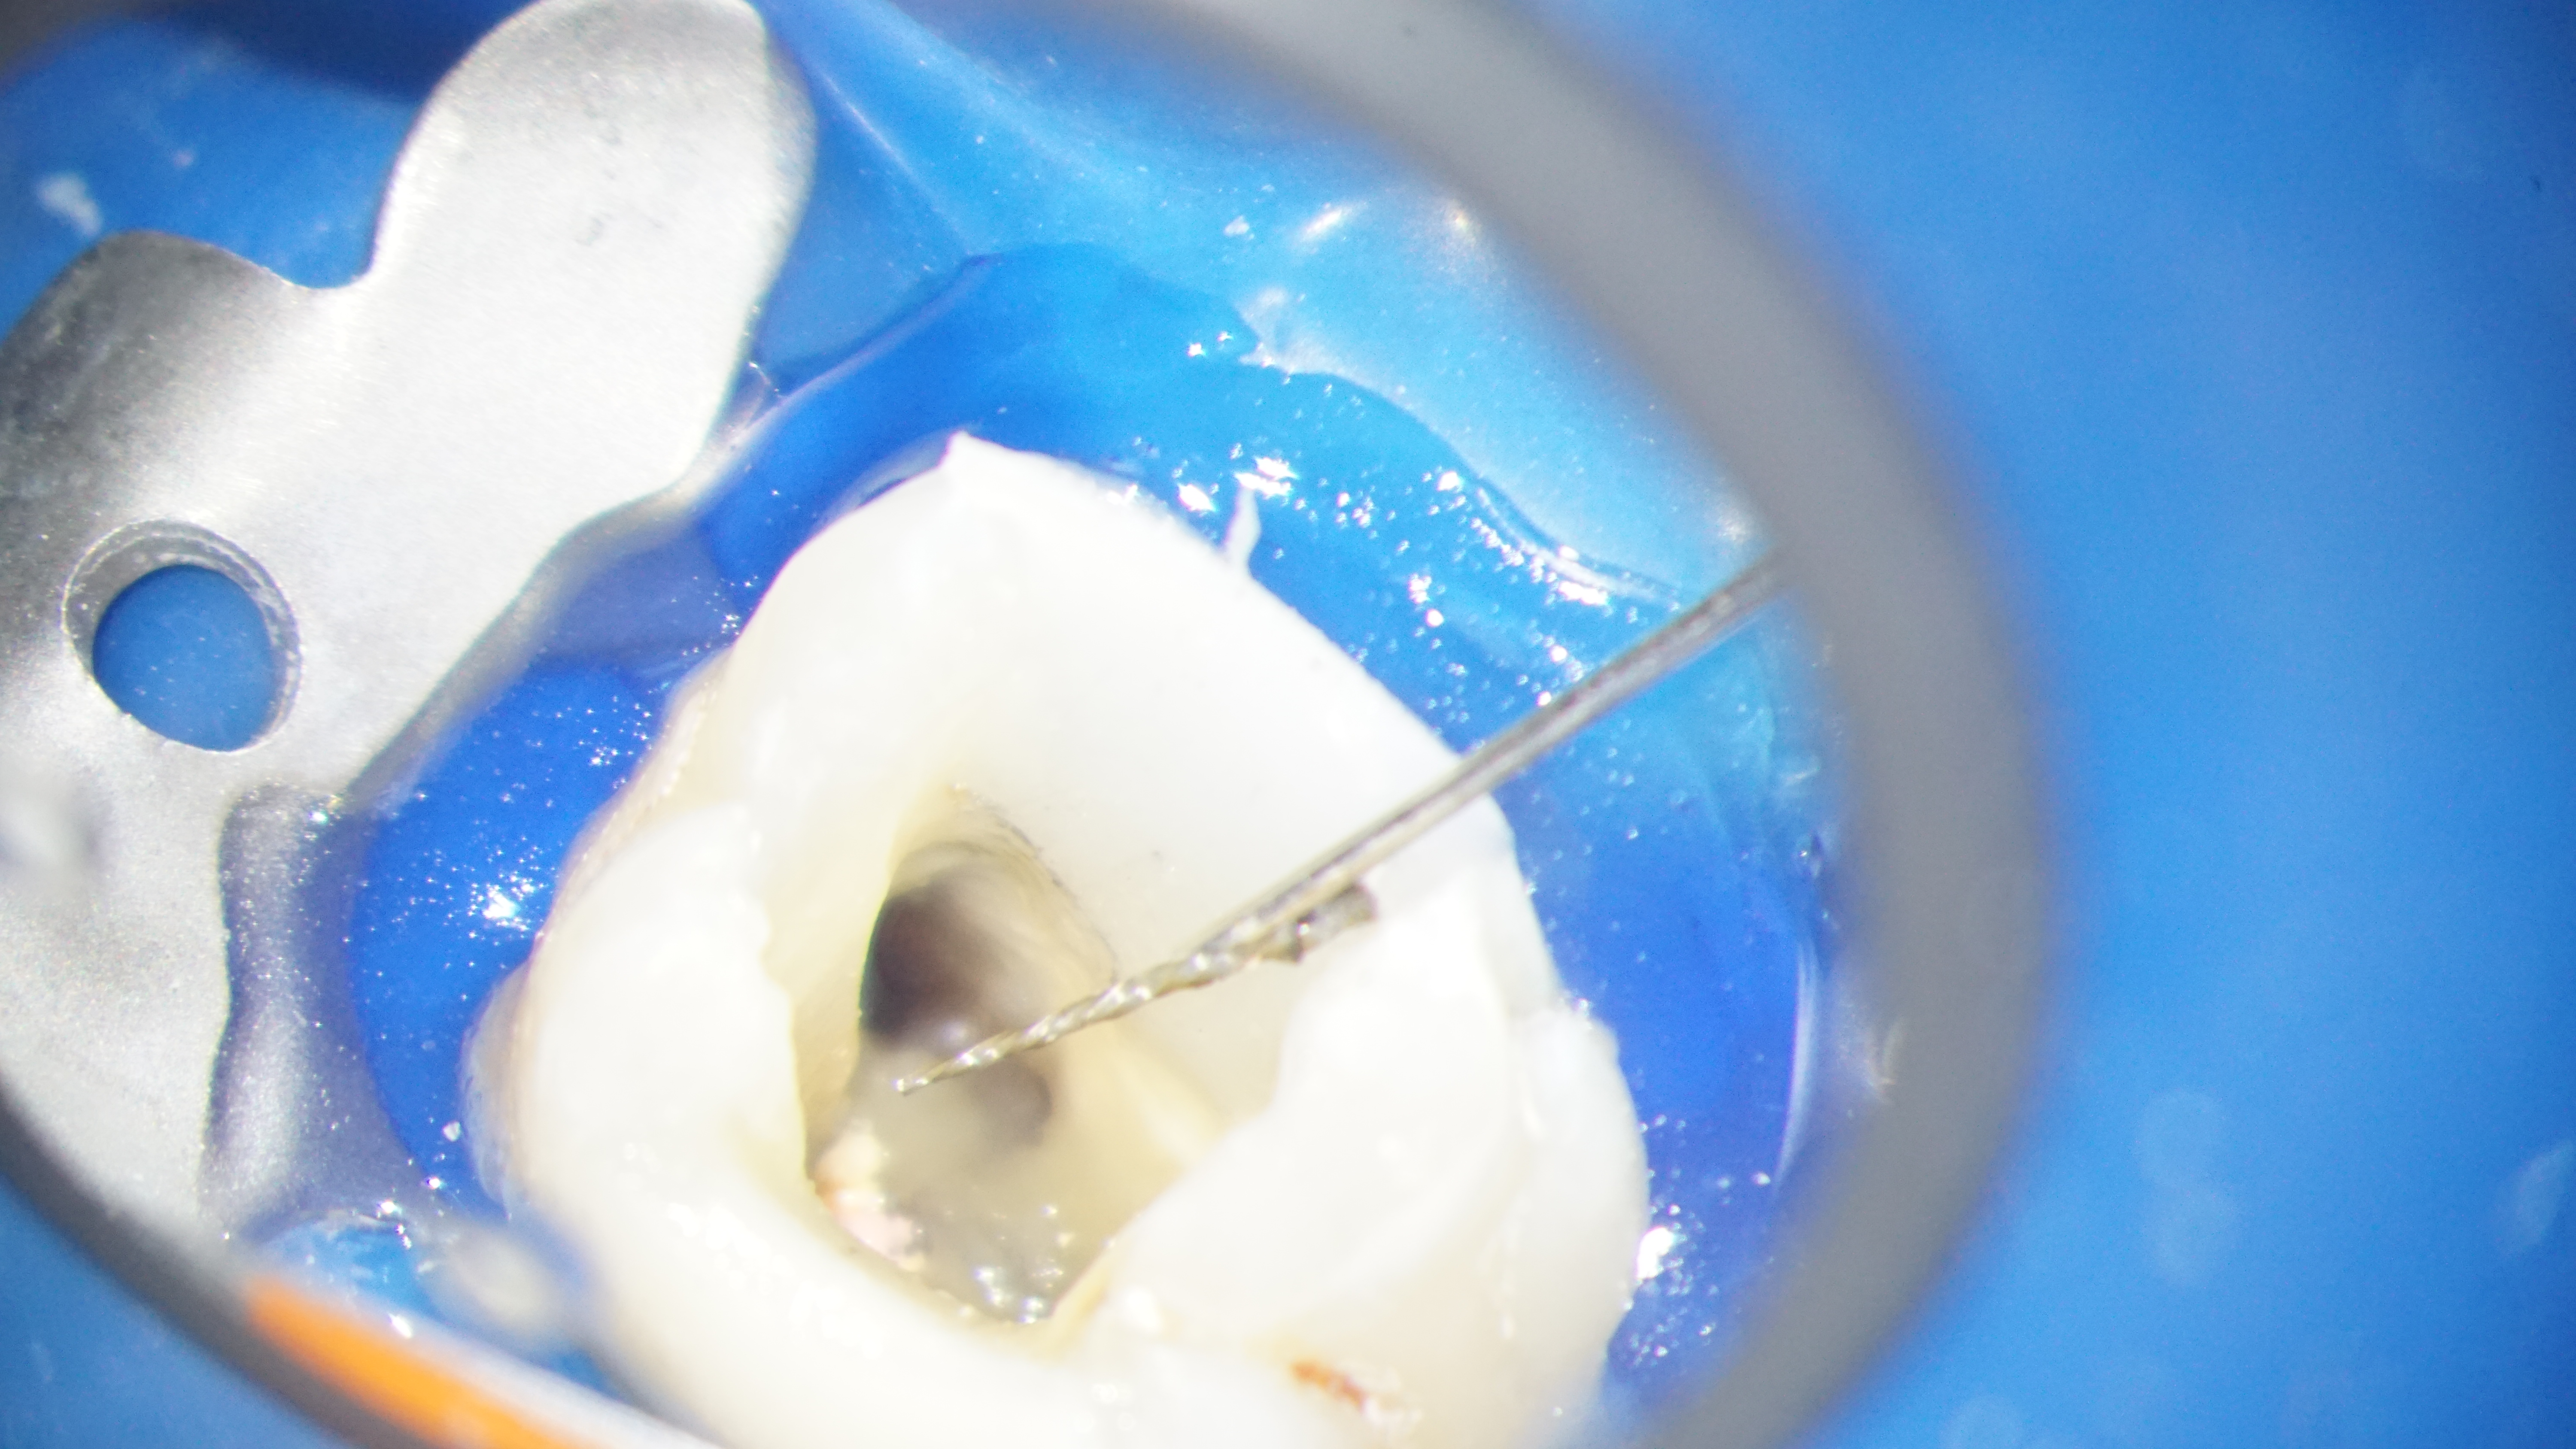

La vizualizarea atenta a canalului putem sa identificam prezenta perforatiei, cu tesut granulomatos si segmentul vizibil din fragmentul separat. Din fericire, reusim sa controlam sangerarea (video 1).

Trecem la manipularea segmentului de ac pentru a-l deplasa in sens coronar, lucru reusit si confirmat atat vizual cat si imagistic (video 2, fig. 3).